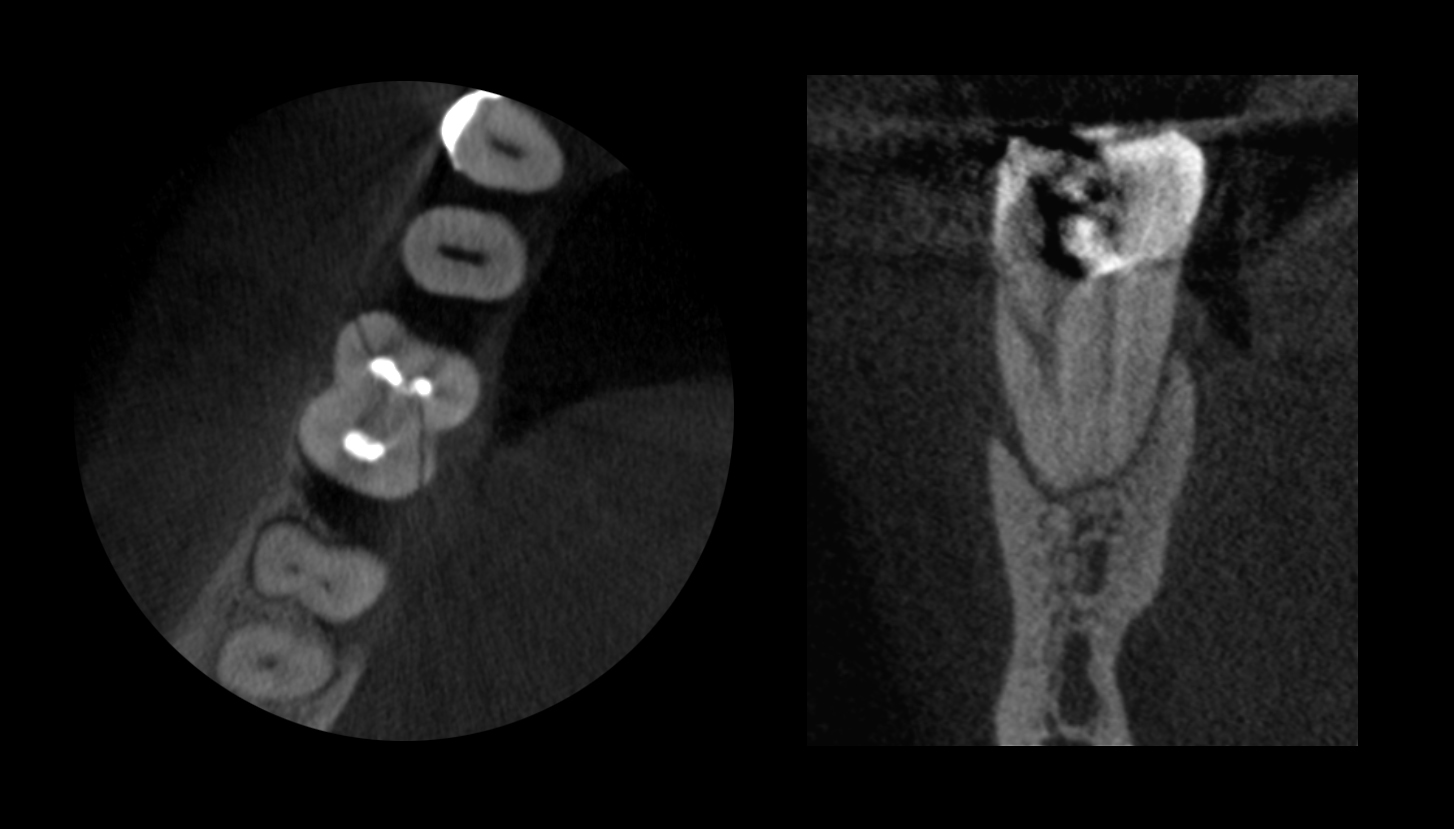

Стоматологическая компьютерная томография (КЛКТ)

3D обследование зубов

Этот тип компьютерного томографа использует особый тип технологии для создания трехмерных (3-D) изображений зубных структур, мягких тканей, нервных путей и кости в черепно-лицевой области за одно сканирование. Конусно-лучевая КТ позволяет более точно планировать лечение. Это также полезно в более сложных случаях, которые включают в себя:

- хирургическое планирование пораженных зубов (например, удаление зубов мудрости).

- для диагностики заболевания височно-нижнечелюстного сустава (ВНЧС).

- точное размещение зубных имплантатов.

- оценка челюсти, пазух, нервных каналов и полости носа.

- обнаружение, измерение и лечение опухолей челюсти.

- определение костной структуры и ориентации зубов.

- определение происхождения боли или патологии.

- цефалометрический анализ.

- реконструктивная хирургия.